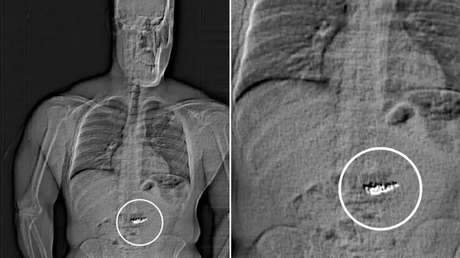

Tras escanear su cuerpo, los detectives encontraron objetos extraños recorriendo su tracto digestivo y determinaron que eran las joyas. Actualmente se enfrenta a cargos de hurto mayor en primer grado y robo con el rostro cubierto.